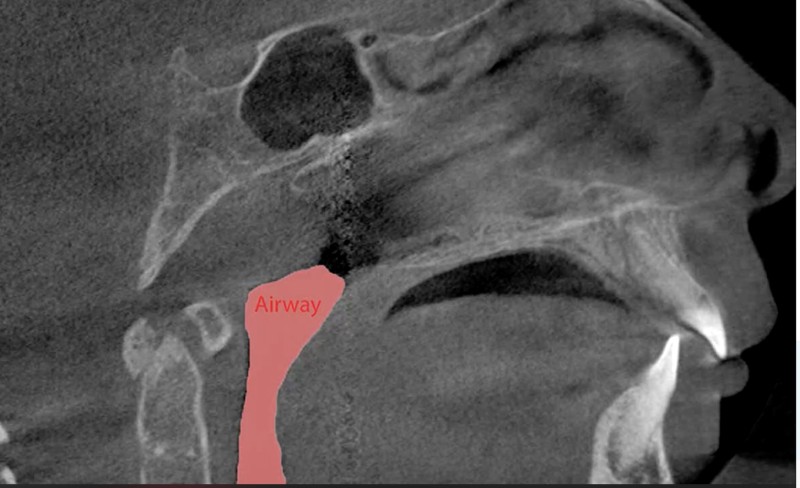

- Increased airway volume 🌬️